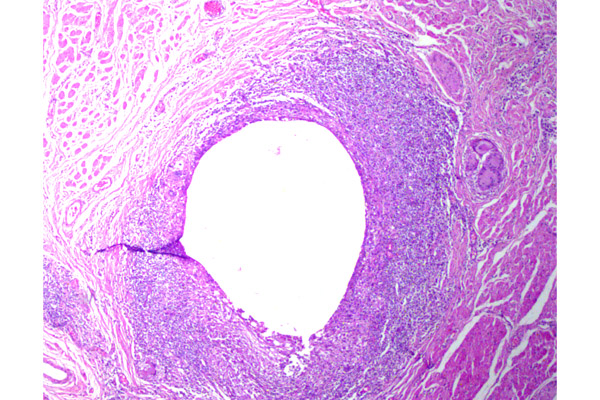

Los granulomas pueden coalescer y constituir estructuras de gran tamaño. La grasa que se encuentra en las glándulas sebáceas (Zeis, Meibomio, etc.) se comporta como un material extraño y desencadena dicha respuesta.

El granuloma está ocupado en casi su totalidad por una gran acumulación de grasa, que se observa como un espacio ópticamente vacío.

El chalazión suele estar rodeado de una cápsula alrededor de la lesión, aunque no se observa fácilmente en todos los casos.